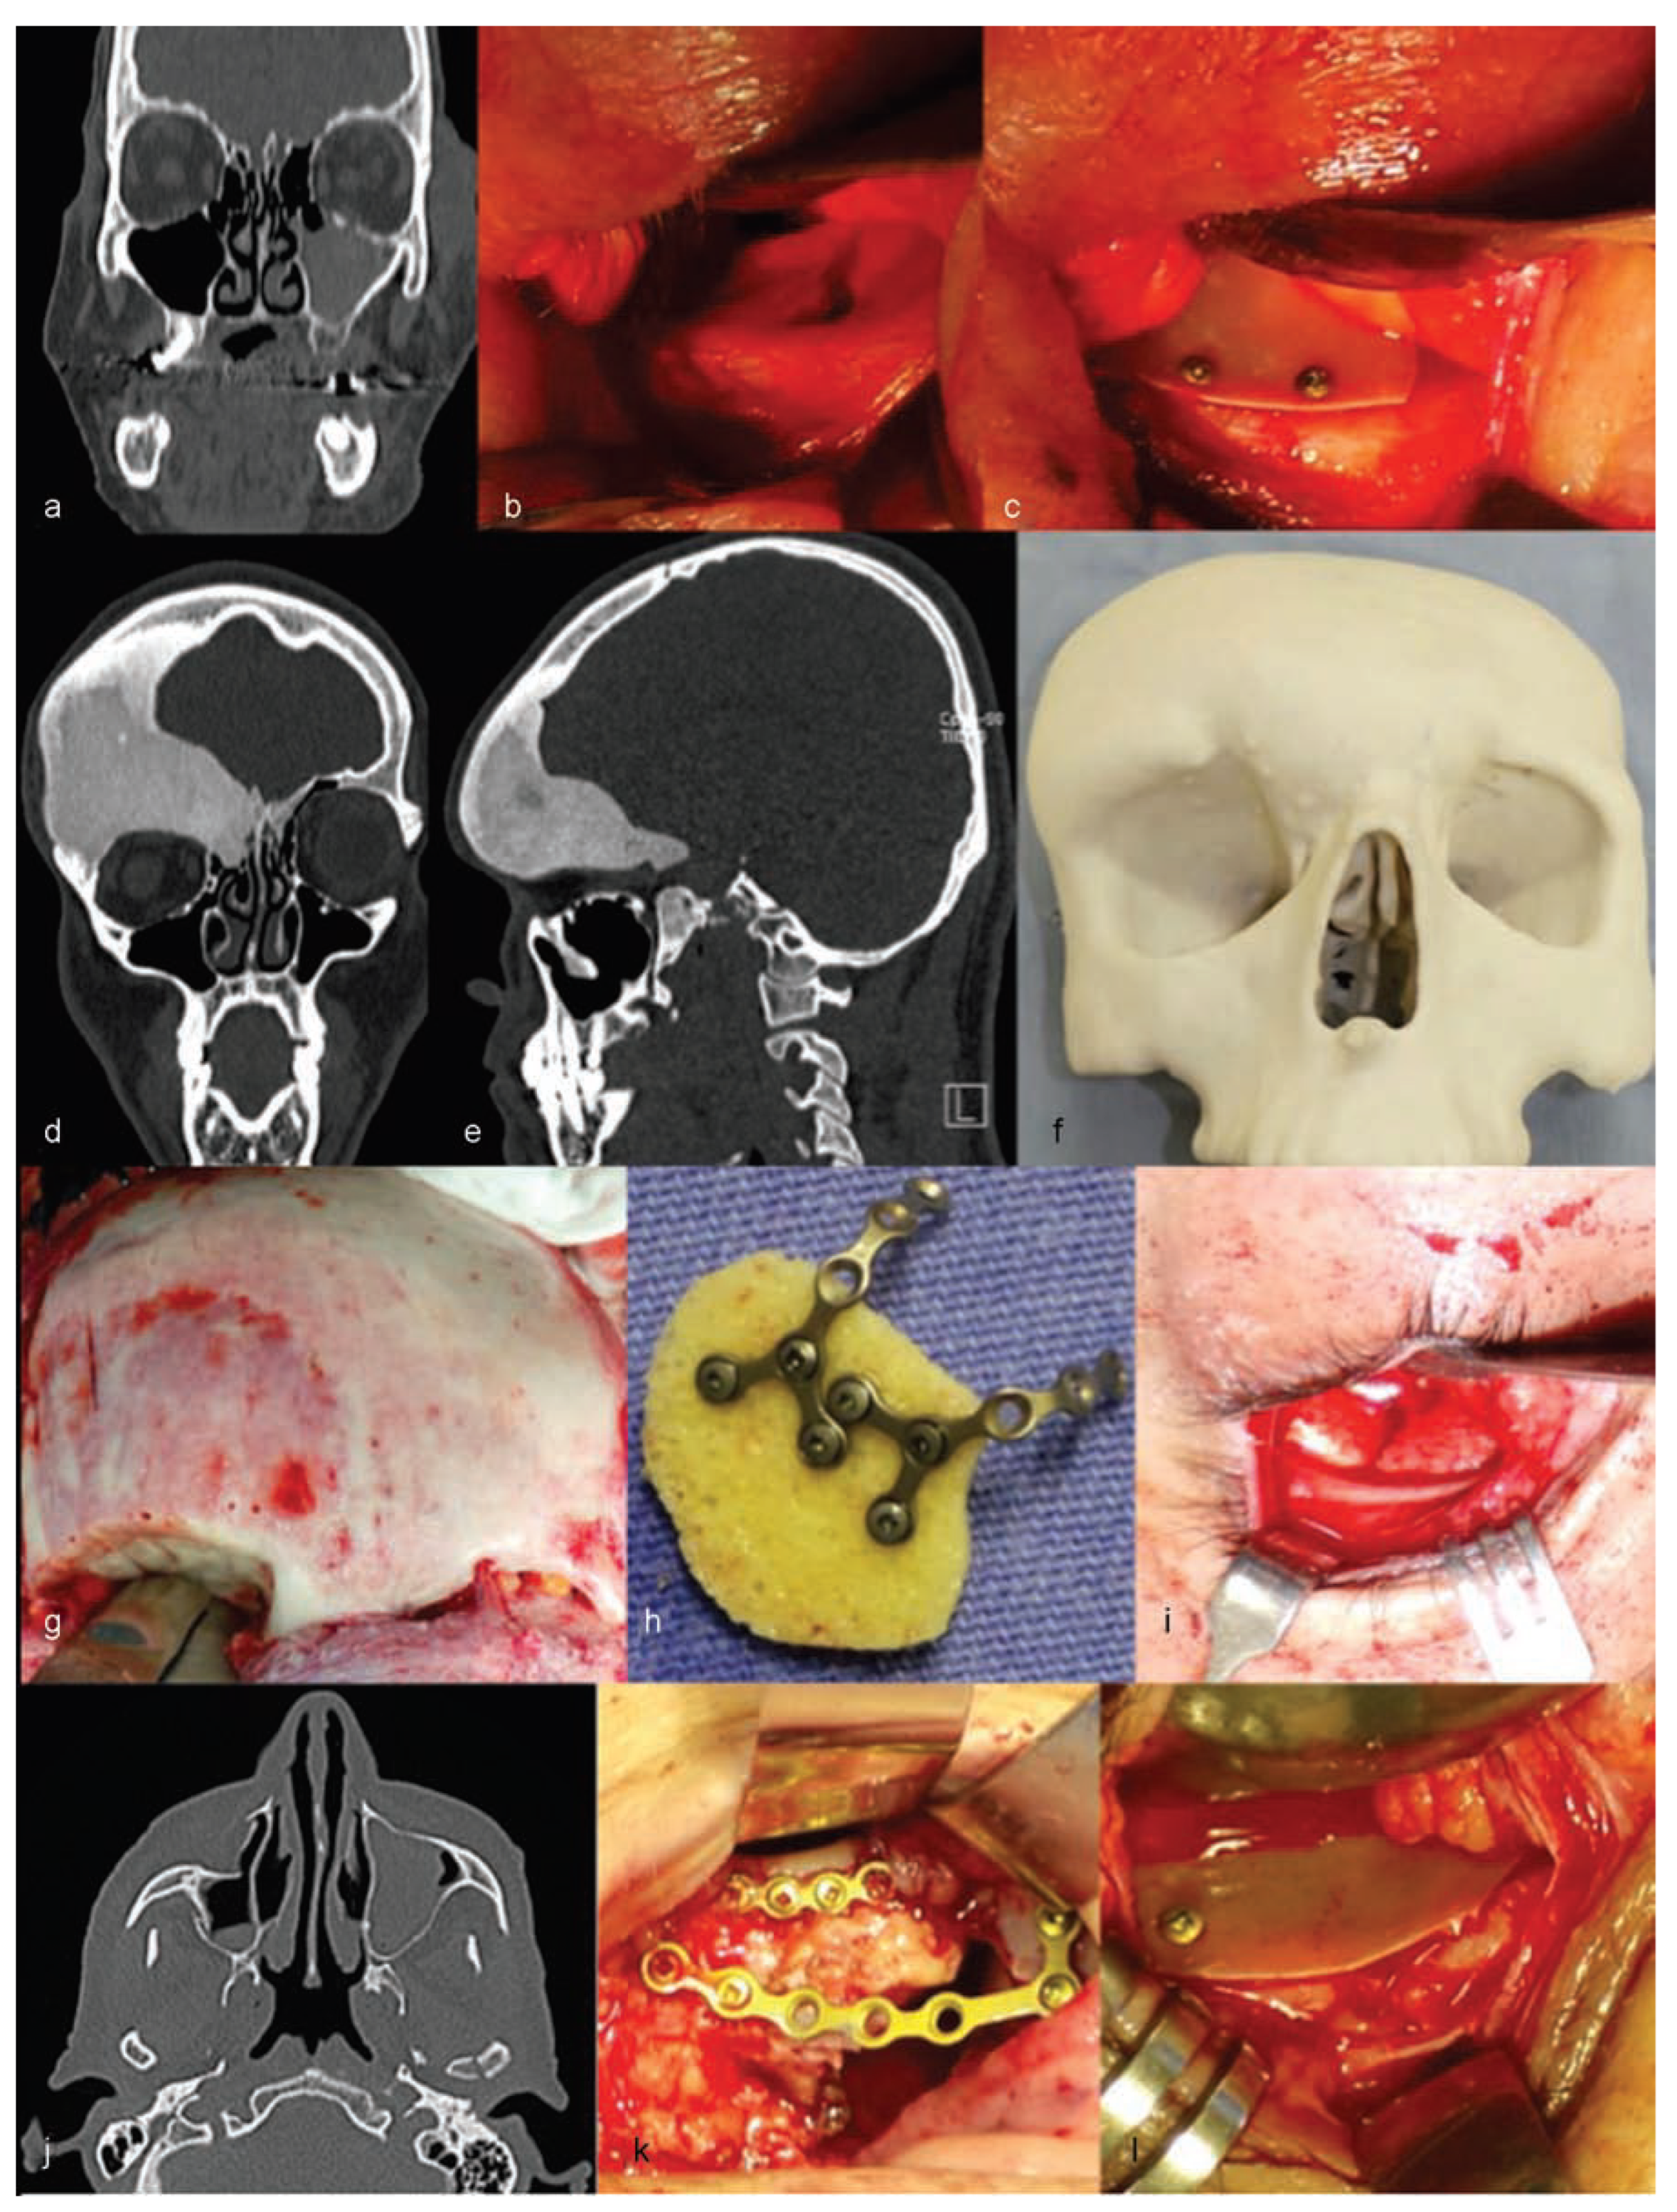

The authors are experienced with the use of castor oil polymer prostheses in several cases of trauma and surgery for camouflage deformities (Figure 1 and Figure 2).

Figure 1. Cases of patients treated with the use of castor oil polymer prosthesis I: (ac,jl) Orbital floor fractures. (di) Orbital deformity due to fibrous dysplasia.